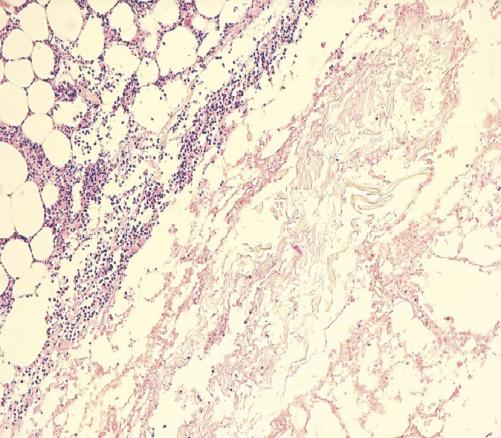

Cette femme de 70 ans, de faible niveau socio-économique, obèse et diabétique de type 2 depuis 20 ans et sous insuline depuis 10 ans, consultait aux urgences pour une douleur de la fosse iliaque gauche. Elle était consciente, tachycarde, fébrile (39,5 °C), et sa glycémie capillaire était à 1,8 g/dL sans cétose. L’examen abdominal notait un placard érythémato-érosif chaud de la fosse iliaque gauche centré par une nécrose bien limitée en carte de géographie (fig. 1 ). La patiente rapportait avoir injecté l’insuline à ce même endroit depuis 3 ans. Le bilan biologique montrait une glycémie à 1,6 g/dL, une hyperleucocytose à 14 500/mm3, une CRP à 130 mg/L et une procalcitonine normale. L’échographie et la tomodensitométrie abdominale montraient un épaississement de la paroi abdominale sans abcès ni collections profondes. Le diagnostic retenu était celui de fasciite nécrosante. Cette patiente était traitée par une antibiothérapie à large spectre avec mise à plat et excision large. L’histologie mettait en évidence des thromboses septiques (fig. 2 ) ainsi qu’une nécrose étendue du derme (fig. 3 ).